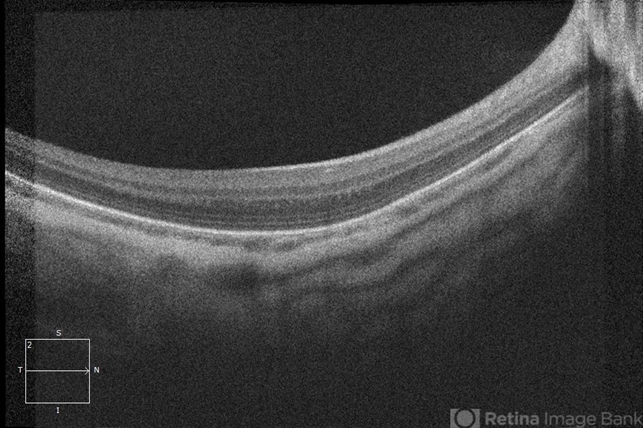

- Oculocutaneous albinism

- albinism, oculocutaneous albinism, optical coherence tomography (OCT), fovea, foveal hypoplasia, nystagmus

- Optical coherence tomography of a patient with oculocutaneous albinism showing a flat fovea.